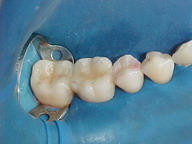

ANTES DEPOIS

Caso acima, em outro ângulo, no momento da cimentação do ONLAY